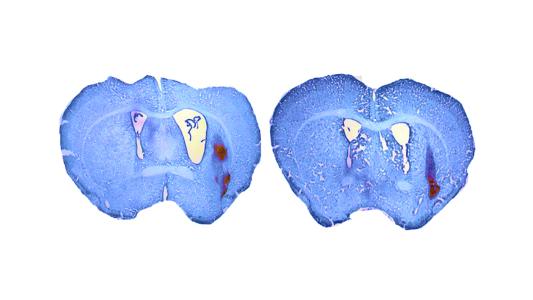

Treatment appears to stop Alzheimer's in monkeys

NYU researchers have modified monkey’s immune system to slow their equivalent of Alzheimer’s disease and improve their cognition.

Editing one gene extends mouse life expectancy by 23%

By modifying just one gene, researchers were able to extend the life expectancy of mice by 23%, and they think their results may translate to humans.